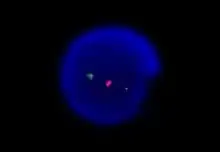

![]() Злокачественные клетки в мазке периферической крови | |

Иммунофенотипирование

Иммунофенотипирование лимфоцитов методом проточной цитометрии обязательно для подтверждения диагноза. Высокочувствительная проточная цитометрия позволяет обнаруживать одну злокачественную клетку на 10 000 нормальных лейкоцитов[15]. В качестве диагностического материала обычно используется периферическая кровь. Для клеток ХЛЛ характерен аберрантный иммунофенотип: одновременная экспрессия (коэкспрессия) Т-клеточного маркера CD5 и В-клеточных маркеров CD19 и CD23[14]. Количество В-клеточных маркеров CD20, CD79b и мембраносвязанных иммуноглобулинов IgM и IgD понижено по сравнению с нормальными В-клетками[3]. В дополнение к этому выявляется клональность. Диагноз ХЛЛ также может быть установлен на основании данных иммуногистохимического исследования биоптата лимфатического узла или селезёнки.

Интерфазная FISH при хроническом лимфоцитарном лейкозе не требует применения митогенов и отличается большей чувствительностью. При анализе используют локус-специфичные зонды, позволяющие выявлять наиболее распространённые хромосомные перестройки (как правило делеции). Этот метод позволяет детектировать хромосомные мутации в более чем 80 % случаев хронического лимфоцитарного лейкоза[16].